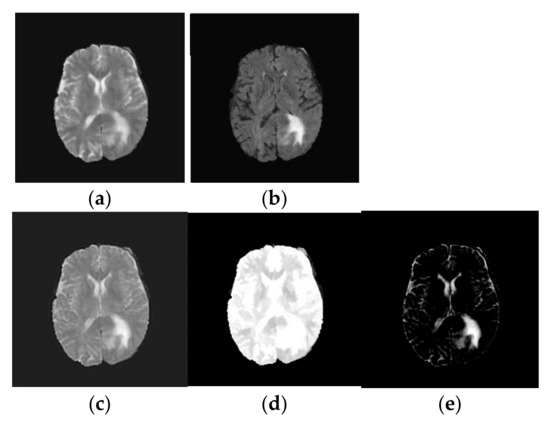

- Image Reconstruction: Finally, the fused low-frequency and high-frequency subbands are recombined using the inverse NSLP. This process reconstructs the final fused MRI image, which is expected to contain the complementary information from both T1-weighted and FLAIR images. The implications of the fused process are shown in Figure 3.

Figure 3. Texture decomposition using TV-L1 approach: (a) T2-weighted brain MRI tumor image; (b) Flair modality brain MRI tumor image; (c) Fused brain MRI tumor image; (d) Geometric component of fused brain MRI tumor image; (e) Texture component of fused brain MRI tumor image.

- TV-L1 Decomposition: The primary objective of our method is to decompose the fused image, into two distinct components: a piecewise smooth (geometric) component and a texture component. The geometric component represents the smooth regions and boundaries of the image, while the texture component captures oscillating features, including edges and noise. In medical imaging, the texture component often contains critical structural details that are essential for tasks such as tumor classification. These structural details can be effectively extracted using the TV-L1-based cartoon-texture decomposition technique. The TV-L1 method separates the fused brain MRI tumor image into two components: the cartoon (geometric) component and the texture component, as outlined in [18]:where gives the cartoon part and which characterizes the geometric component of the fused image. Similarly, represents the texture part of the fused image. The cartoon component of the fused image is attained by minimizing the following objective function [18]:where represents the gradient operator and λ defines the regularization criteria which is a trade-off between the fidelity criteria and regularization term. In this work, we chose λ as 0.1. Similarly, denotes the image domain and the symbol represents L1 normalization. The first part of Equation (2) represents the TV of cartoon component and the second part specifies the fidelity to make the cartoon part keep close to the fused image, and they are calculated over the image domain Ω. The solution to Equation (2) is resolved by the following optimization [19]:where and represent the forward and backward differences. provides the magnitude of gradient. The parameter l provides the iteration index. In this, we chose l as 50. is defined as changes in time, and and indicate discrete spatial distances of the image grid. φ and ε (0.00001) are constants. The resultant outcome of TV-L1 decomposition is shown in Figure 3.